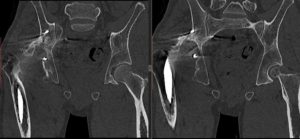

Позволяет обнаруживать очаги уплотнения и разрежения, оценивать размеры, форму, расположение и распространенность патологических участков, выполнять трехмерную реконструкцию исследуемой зоны. Мскт костей таза проводится для уточнения характера повреждений при травмах таза (переломах, инородных телах).

МСКТ всех костей таза осуществляется без наркоза. Возможность получения сверхтонкого среза на аппарате последнего типа обеспечивает выявление недуга на ранних стадиях, что важно при диагностировании опухолевых процессов. Создание трехмерной модели костей таза помогает обнаружить все изменения и составить дальнейший план и прогнозы лечения.

Смоделированный снимок исследуемого участка тела позволяет уточнить характер травмы и повреждений, увидеть инородный предмет. Также Кт костей таза должна применяться для диагностики рака и метастазирования. Метод показан при аномалии анатомических участков и остеопорозе костей таза. Томограмма костей таза необходима при недугах, которые разрушают костные ткани.

Процедура МСКТ позволяет проводить трехмерную реконструкцию костей и суставов, используется для диагностики и изучения переломов, активно применяется при обосновании необходимости хирургического вмешательства и дает возможность визуализировать диски, мышцы, связки для выявления текущего состояния костной системы.